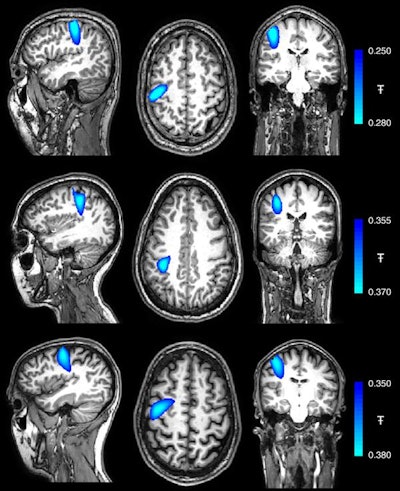

The researchers used these images, as well as data from a motion-tracking camera, to coregister the location and orientation of the helmet OPMs relative to the participants' head. This technique ultimately allowed them to generate 3D images representing changes to beta brainwave activity.

Despite the substantial head movement that these tasks required, the MEG scanner was able to record clear electrophysiological responses in the brain. Of note, the largest change in brain activity while the participants performed their respective tasks occurred in the contralateral primary somatosensory cortex of the brain.